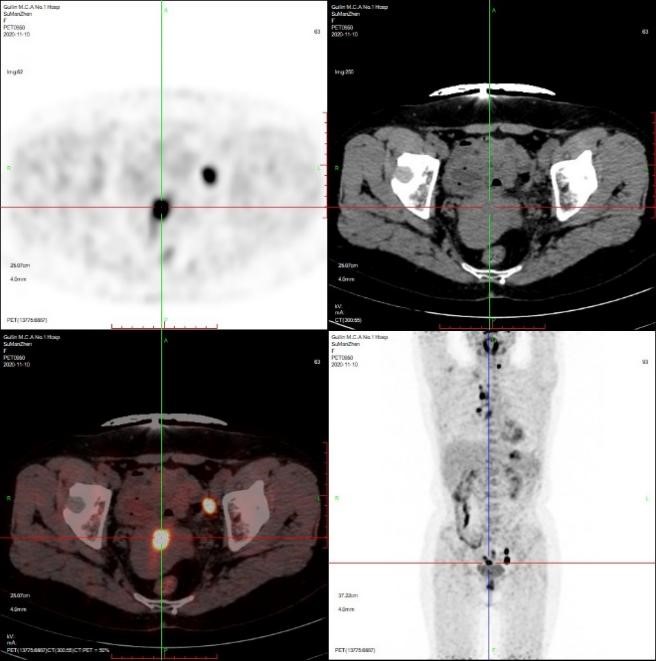

患者粟女士,57岁,既往甲状腺乳头状癌病史6年,近1月来反复咳嗽,当地CT提示肺部占位,为进一步明确诊断,至附属医院核医学科行PET/CT全身检查,提示颈部淋巴结、双肺及子宫内膜多发异常高代谢病灶。

之后根据PET/CT子宫内膜摄取病灶定位,协助妇科获取了相应部位子宫内膜病理组织。术后完成病理定性、肿瘤组织学亚型分类、分子病理检测。病理提示颈部淋巴结为甲状腺乳头状癌颈部淋巴转移;肺占位为腺泡型肺腺癌(免疫组化支持肺原发来源)。子宫内膜病理提示子宫内膜癌。

患者全身PET/CT图像